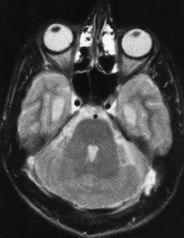

SPECT cerebral con 99mTc-HMPAO en una paciente diagnosticada de megacisterna magna

Fernández, Mora, Ricart , Castell, Benítez, Muñoz, Martín-Comín

Rev Esp Med Nucl Imagen Mol 1999;18:110